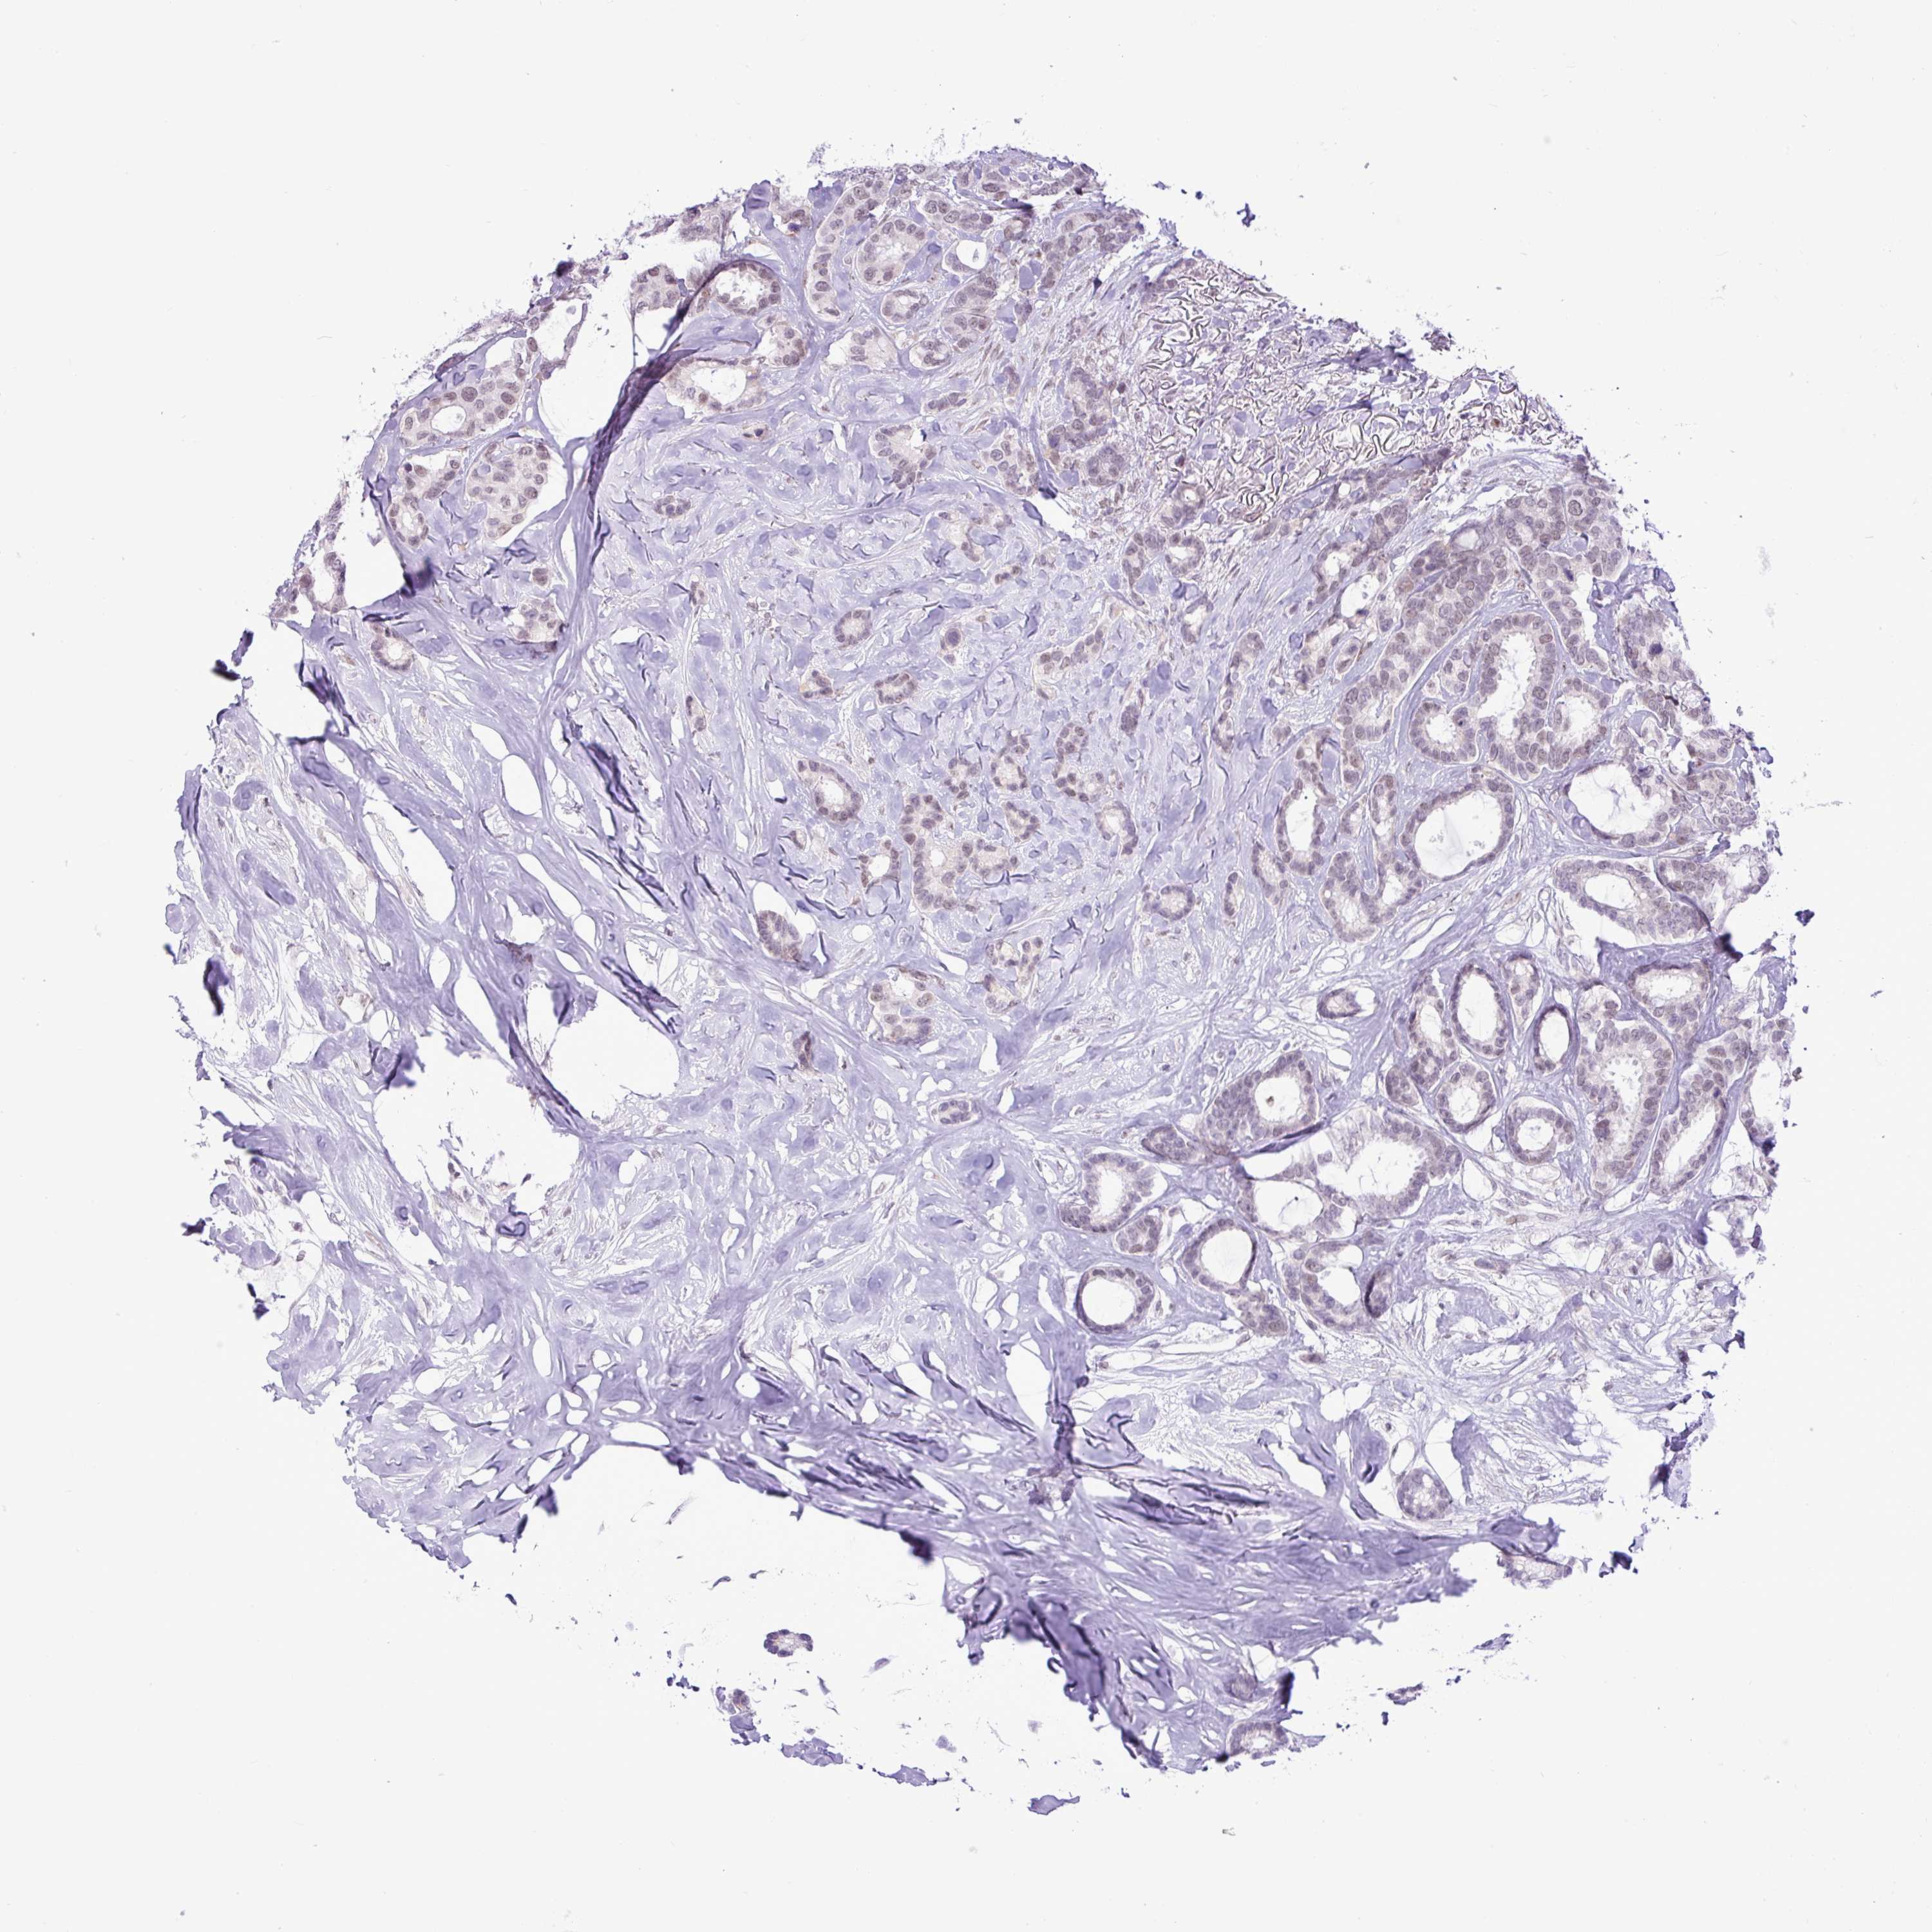

CANCER BREAST CANCER Show tissue menu

BRCA TCGA BRCA VALIDATION PROTEIN EXPRESSION